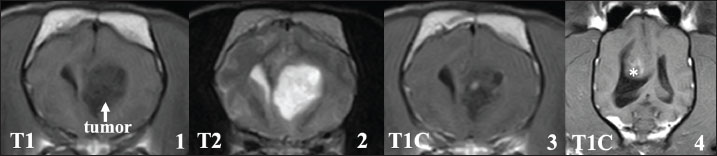

Brain tumors in all 15 cases were present in the cerebrum and were suspected to be tumors derived from glial cells (Fig. 1). Among the 15 cases, 14 cases had a single tumor site, and one case had 2 tumor sites in the cerebrum on MRI. Furthermore, 11 of the 15 cases appeared to be in contact with the lateral ventricles, and in 3 cases, the tumor tissues seemed to invade into the lateral ventricles on MRI. Although the signal intensity on MRI of these glial tumors varied, most cases showed low to iso-signal intensity on T1-weighted images and iso- to high-signal intensity on T2-weighted images. The enhancing effect of the contrast medium also varied among the cases; one case showed a clear ring-enhancing effect, 2 cases showed homogenous enhancement (one case with a ring-shaped periphery), and 7 cases showed heterogenous enhancement (three cases with a ring-shaped periphery). The remaining 5 cases showed almost no enhancement. Cerebellar herniation, possibly induced by the intracranial tumor, was observed in two cases. Additional CT evaluations of the thoracic and abdominal cavities at the first visit showed no distant metastatic lesions and other abnormal findings in any of the patients.

Fig. 1. Typical MRI findings of the presumed glial tumors observed in this study. In many cases, brain tumors showed low signal intensity on T1-weighted images (1) and high signal intensity on T2-weighted images (2). Various enhancing effects were observed in the contrast examination, but most of them showed relatively weak enhancement (3). Some tumor tissues that clearly protruded into the ventricles were also observed (4, asterisk).